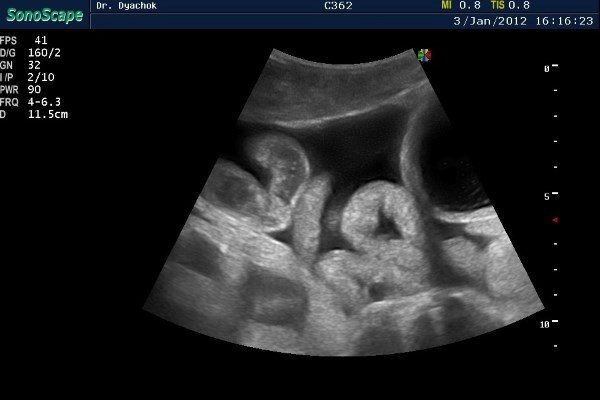

Ультразвуковое обследование кишечника проводится иначе, чем осмотр плотных органов. Чтобы ультразвук задержался на стенке кишки, ее нужно заполнить водой. Существует несколько способов проведения процедуры.

- Трансабдоминальный. Наиболее часто используемый метод УЗИ, для которого и требуется заполнение кишечника жидкостью. Осмотр врач делает через брюшную стенку.

- Эндоректальный метод УЗИ кишечника подразумевает осмотр через прямую кишку. Обладает большей точностью, не требует введения жидкости. Но объем исследования ограничен, возможно осмотреть лишь толстый кишечник.

- Трансвагинальный метод. Осмотр производится через влагалище. Используется только у взрослых женщин, когда недоступны другие способы.

Трансабдоминальное УЗИ проводится трехэтапно. Сначала пациента осматривают натощак с пустым кишечником. Затем с помощью клизмы кишку заполняют водой, снова делают осмотр. Последний этап — осмотр после выведения жидкости.

После проведения УЗИ кишечника врач определяет, что показывает снимок. Оценивается состояние кишечной стенки, длина и ширина органа, расположение петель.

Здоровый кишечник имеет форму полого цилиндра. У тонкой кишки контуры ровные и гладкие, диаметр от 3 до 6 см. Длина ее около 2 метров. Толщина стенки не более 7 мм.

Толстая кишка имеет диаметр 6-8 см, длину чуть более 2 метров. Стенка ее образована пятью слоями, толщина которых достигает 1 см. Толстая кишка не ровная, а имеет перетяжки, которые называются гаустры.